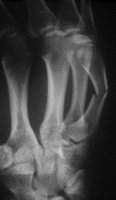

Schaftfraktur des 5. Mittelhandknochen durch schlag. Der Patient hat eine Nickelallergie. Hier wird die Fraktur in i.V. - Anästesie reponiert und mit einem 2mm Titandraht stabilisiert. Diese Versorgung ist stabil genug für eine frühfunktionelle Behandlung. Vorteil ist auch hier, dass es nicht zur Bewegungsbehinderung im Grundgelenk kommt.